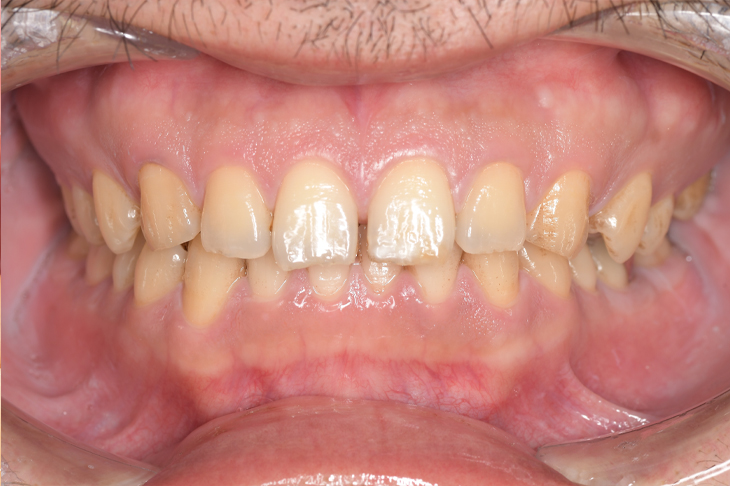

CASE 7

基本情報

| 年齢・性別 | 48歳・男性 |

| 主訴 | 定期検診 |

| 治療内容 | スケーリング |

| 治療期間 | 60分 |

| 治療費 | 1,500円(保険診療) |

| リスク・副作用 | 知覚過敏、出血 |

| 治療方針 | まず歯肉縁上歯石を除去して、スッキリとした感覚や滑らかな舌ざわりを実感してもらいました。この状態を保てるように歯磨きの仕方や、歯周病についてお話ししました。 今後は歯肉縁下歯石を除去して、歯周病治療を行っていきます。 |

| 担当者所見 | 久しぶりの歯科医院への受診でした。 治療に慣れていないため、少しずつ歯石を除去していきました。 |